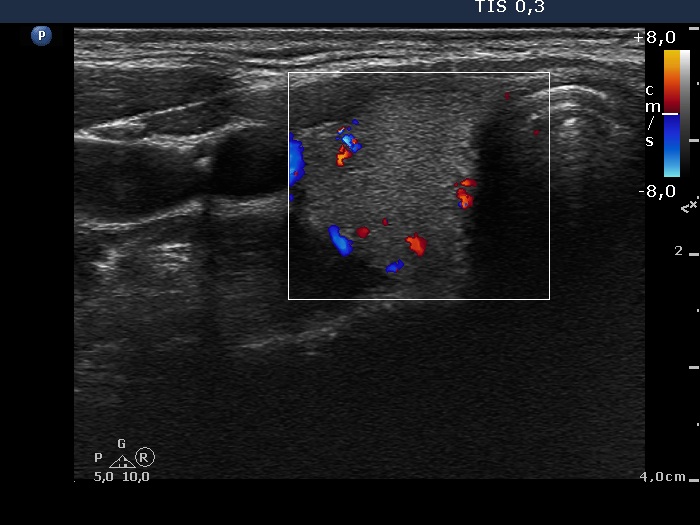

Right lobe, transverse scan

- There are two situations in Graves 'disease where circulation is increased. At the stage of disease activity and when hypothyroidism is observed with medication. In the former case, the blood flow is almost always increased, in the latter it can be decreased and increased.